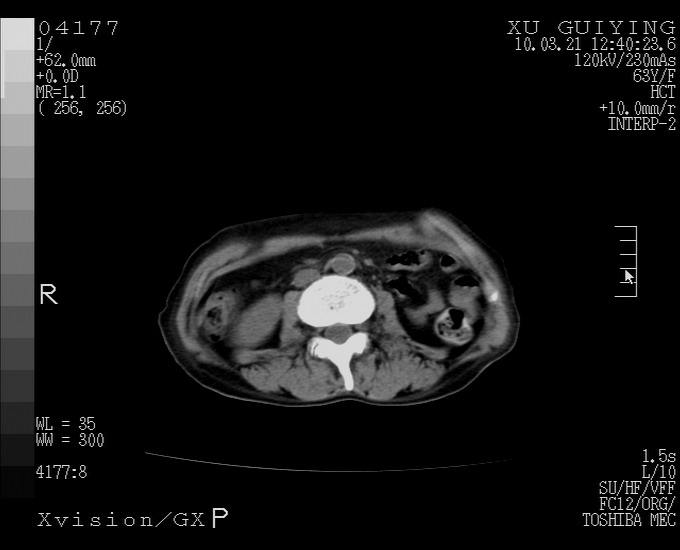

标题: CT25230:女,63岁,萎缩性胃炎病史,患者明显黄染,不能进 [打印本页]

标题: CT25230:女,63岁,萎缩性胃炎病史,患者明显黄染,不能进

怎么没有增强呢?胆囊那么大,密度有些高啊。

慢性胆囊炎,胆囊占位不排除,建议增强或彩超。

考虑胆囊炎 不除外泥沙样结石

胆囊体积增大,胃窦壁增厚

胆囊体积增大,密度不均匀,结石不除外;胃壁增厚,考虑胃癌,建议增强。

胆囊体积增大,密度增高,较均匀,外缘也较光滑,应考虑胆囊炎。因为胃未充盈,不好说壁增厚。肝左叶及脾门处见低密度灶,有可能是血管瘤,不排除囊肿。建议超声检查或强化。

这就是江湖人称的“内科黄疸”, 肝内胆汁淤积症(ic)?